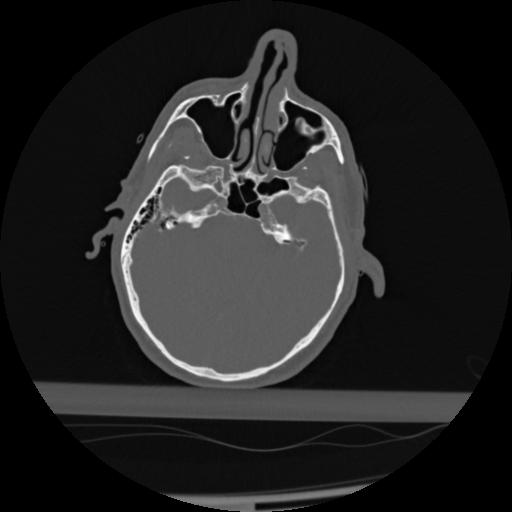

22 ANGIO,CE,Vol,0.5,ANGIO,,